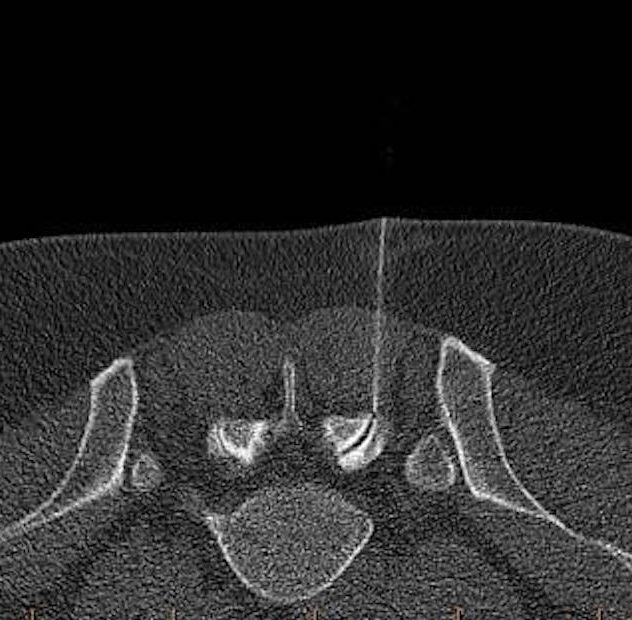

Epidural Steroid Injection

An Epidural Steroid Injection (ESI) is a safe, minimally invasive treatment that helps reduce spine-related pain and inflammation. We use advanced imaging (CT Guidance) to precisely target the affected area, often for conditions like herniated discs, sciatica, or spinal stenosis.

CT Guidance allows us to use a thinner needle and more precise targeting to guarantee placement and minimize pain from the procedure.

CT imaging provides a 360-degree, cross-sectional view of your spine and anatomy. We can see the needle tip in real-time, ensuring it is placed within millimeters of the target nerve or joint.

Because CT scans visualize soft tissues and blood vessels—not just bone—we can navigate around sensitive structures that are invisible on standard X-rays. This significantly reduces the risk of complications.